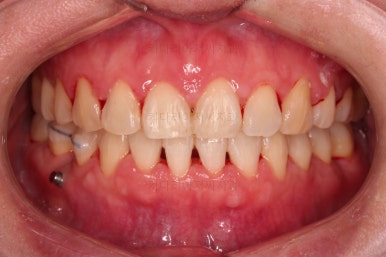

4. 마무리

위아래 좌우 치아가 없는 위치가 모두 달랐지만 교합도 잘 구성했고요.

아무래도 좌우 치아 크기들이 다르다 보니(뽑은 치아가 다르니) 중앙선은 100% 일직선은 안맞더라도 매우 정상 범주로 마무리를 할 수 있었습니다.

특히 어금니에 보이던 충치도 깔끔하게 마무리 했고요.

이제 부산교정치과 전후 비교해 보겠습니다.

치아배열, 틈새, 교합, 중앙선, 입매, 심지어 충치까지 깔끔히 잘 마무리 되었습니다.